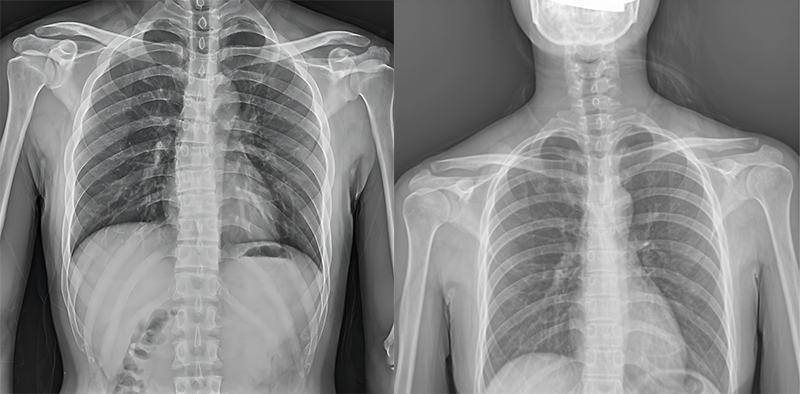

百微米DR与普通像素尺寸DR的影像对比

以胸部摄影为例,通过对比百微米大平板与普通像素尺寸平板的影像,可以看到百微米影像对比度适中,图像清晰度更高,成像细节更加丰富。在胸部影像显示中肺门影结构、肺纹理等细节展示更清楚,两侧膈肌边缘、心脏、纵隔边缘清晰锐利显示,在影像中都可以清晰地显示胸部细微结构,满足临床诊断要求。